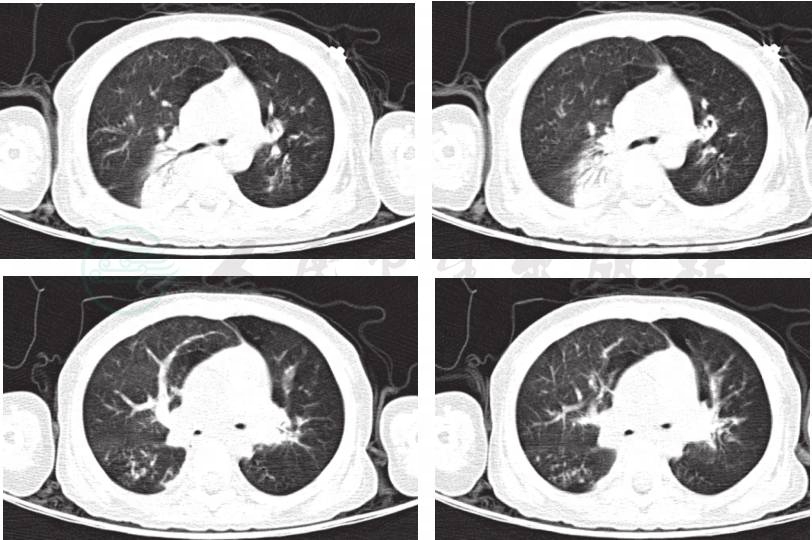

辅助检查:肺CT(当地医院,入院前2周)(图1):双肺透过度不均匀,双肺炎症,右肺部分实变。肺CT(笔者医院门诊)(图2A,图2B):双肺透过度不均匀,呈马赛克征改变,多叶段炎症,右肺部分实变,双肺散在肺气囊形成。

图2A 入院前笔者医院门诊肺CT

图2B 入院前笔者医院门诊肺CT